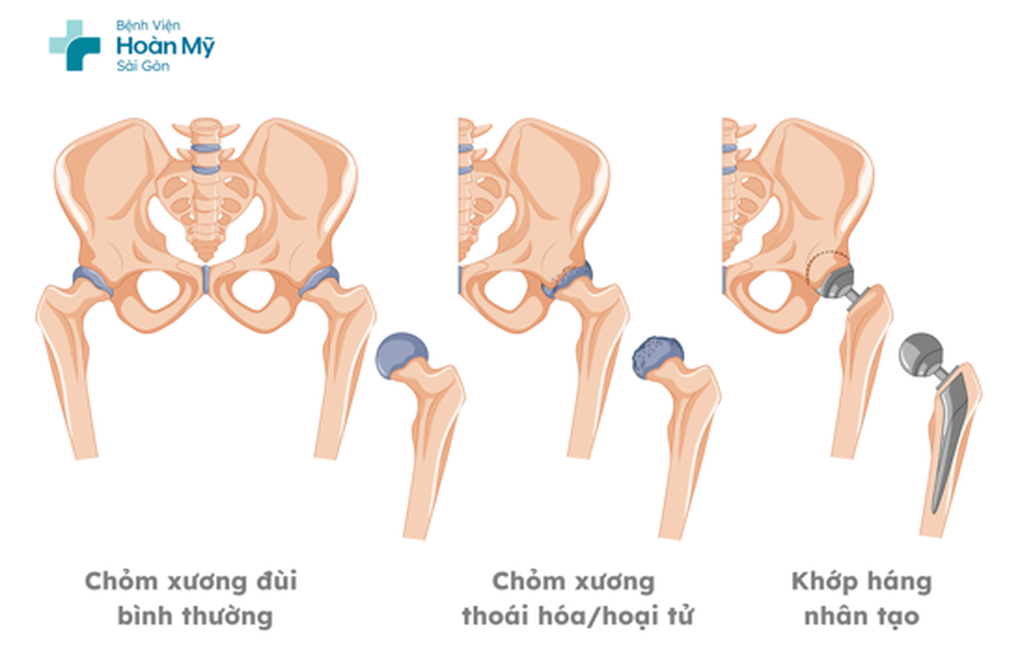

Hoại tử chỏm xương đùi là tình trạng mất nguồn máu nuôi cung cấp đến chỏm xương đùi, khiến tế bào xương chết dần và cấu trúc nâng đỡ bị suy yếu. Khi phần xương bên trong không còn bình thường, bề mặt khớp của xương đùi rất dễ xẹp, biến dạng co rút, từ đó gây đau và mất khả năng đi lại.

Việc thay khớp háng toàn phần được chỉ định nhằm phục hồi lại hình dạng của khớp, giảm đau hiệu quả và giúp người bệnh sớm quay trở lại lao động sinh hoạt như bình thường.

Trong khi đó, khớp háng phải vẫn còn khả năng bảo tồn (không thay khớp), phù hợp với phương pháp phẫu thuật giảm áp cổ xương đùi. Mục đích của phương pháp này là làm giảm áp lực bên trong xương, cải thiện tuần hoàn vùng chỏm và làm chậm quá trình hư khớp.

Ảnh minh họa xương chỏm đùi bị thoái hóa nặng có thể được chỉ định thay khớp nhân tạo (Ảnh: BVCC).